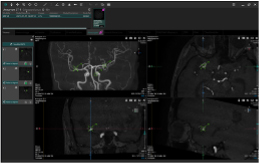

画像統合ビューア(Findings Workflow)

各種解析結果を画像観察に最適なレイアウトで表示し,一貫したユーザーインターフェイスで確認することが可能です。

EIRL Chest CT |

EIRL Chest Screening |

Temporal Subtraction For Bone |

EIRL Brain Aneurysm |

Ischemia analysis |

Brain Perfusion |